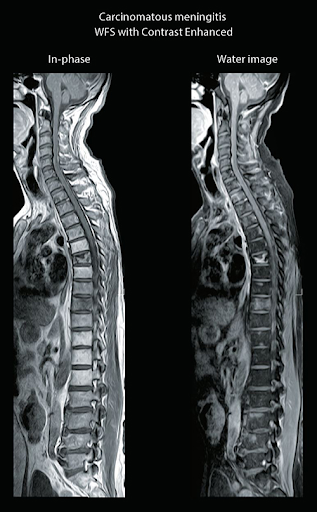

Water Fat Separation обеспечивает однородные изображения с сохранением четырех разных контрастов тканей за одно сканирование, сокращая количество необходимых исследований. Может использоваться для исследования любой части тела.

WFS2 DIXON (FSE2D)